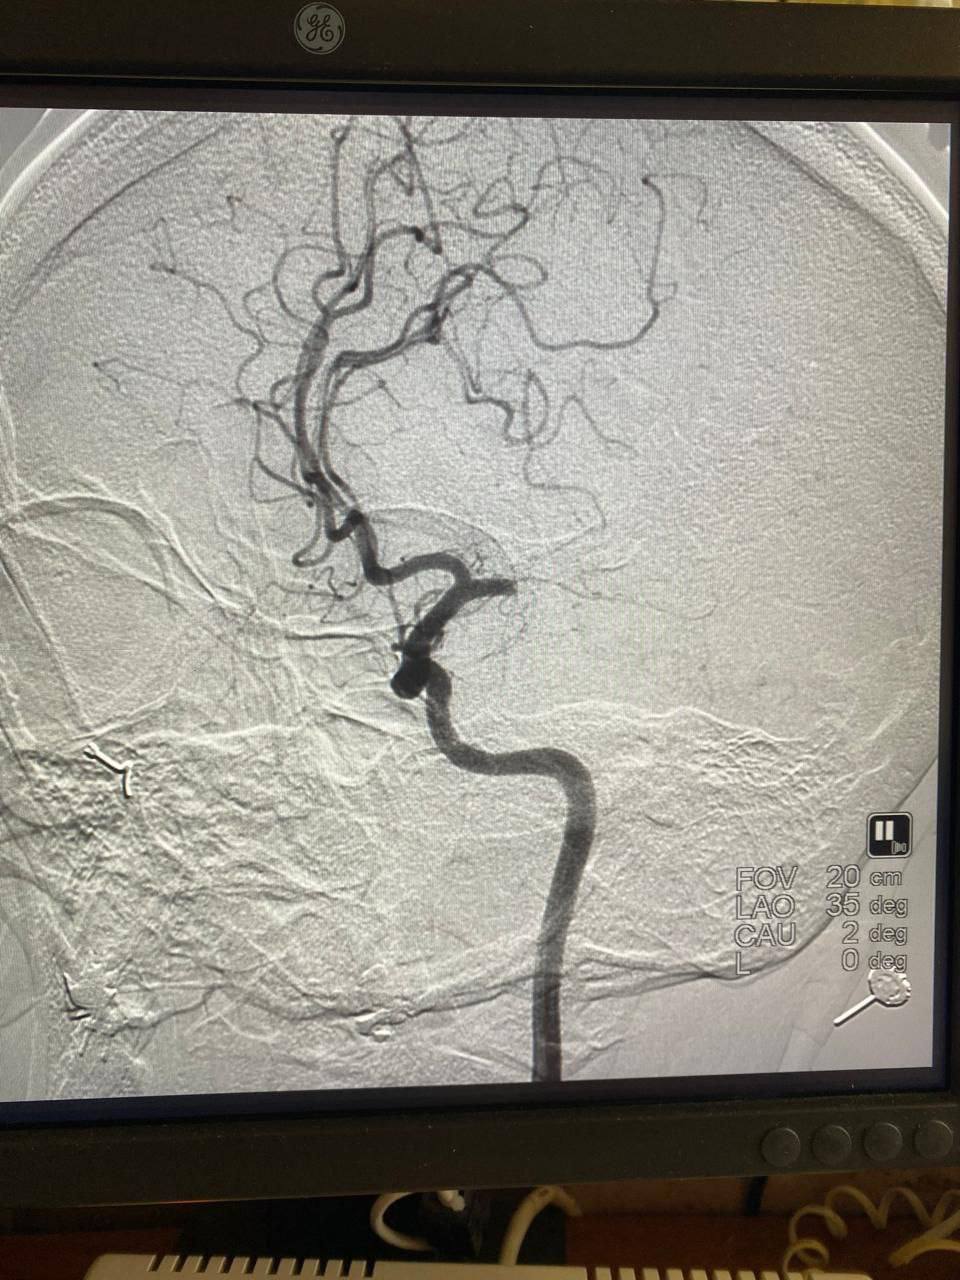

Пациентку экстренно отправили в рентген-операционную. Врачи удалили тромб и восстановили мозговой кровоток.